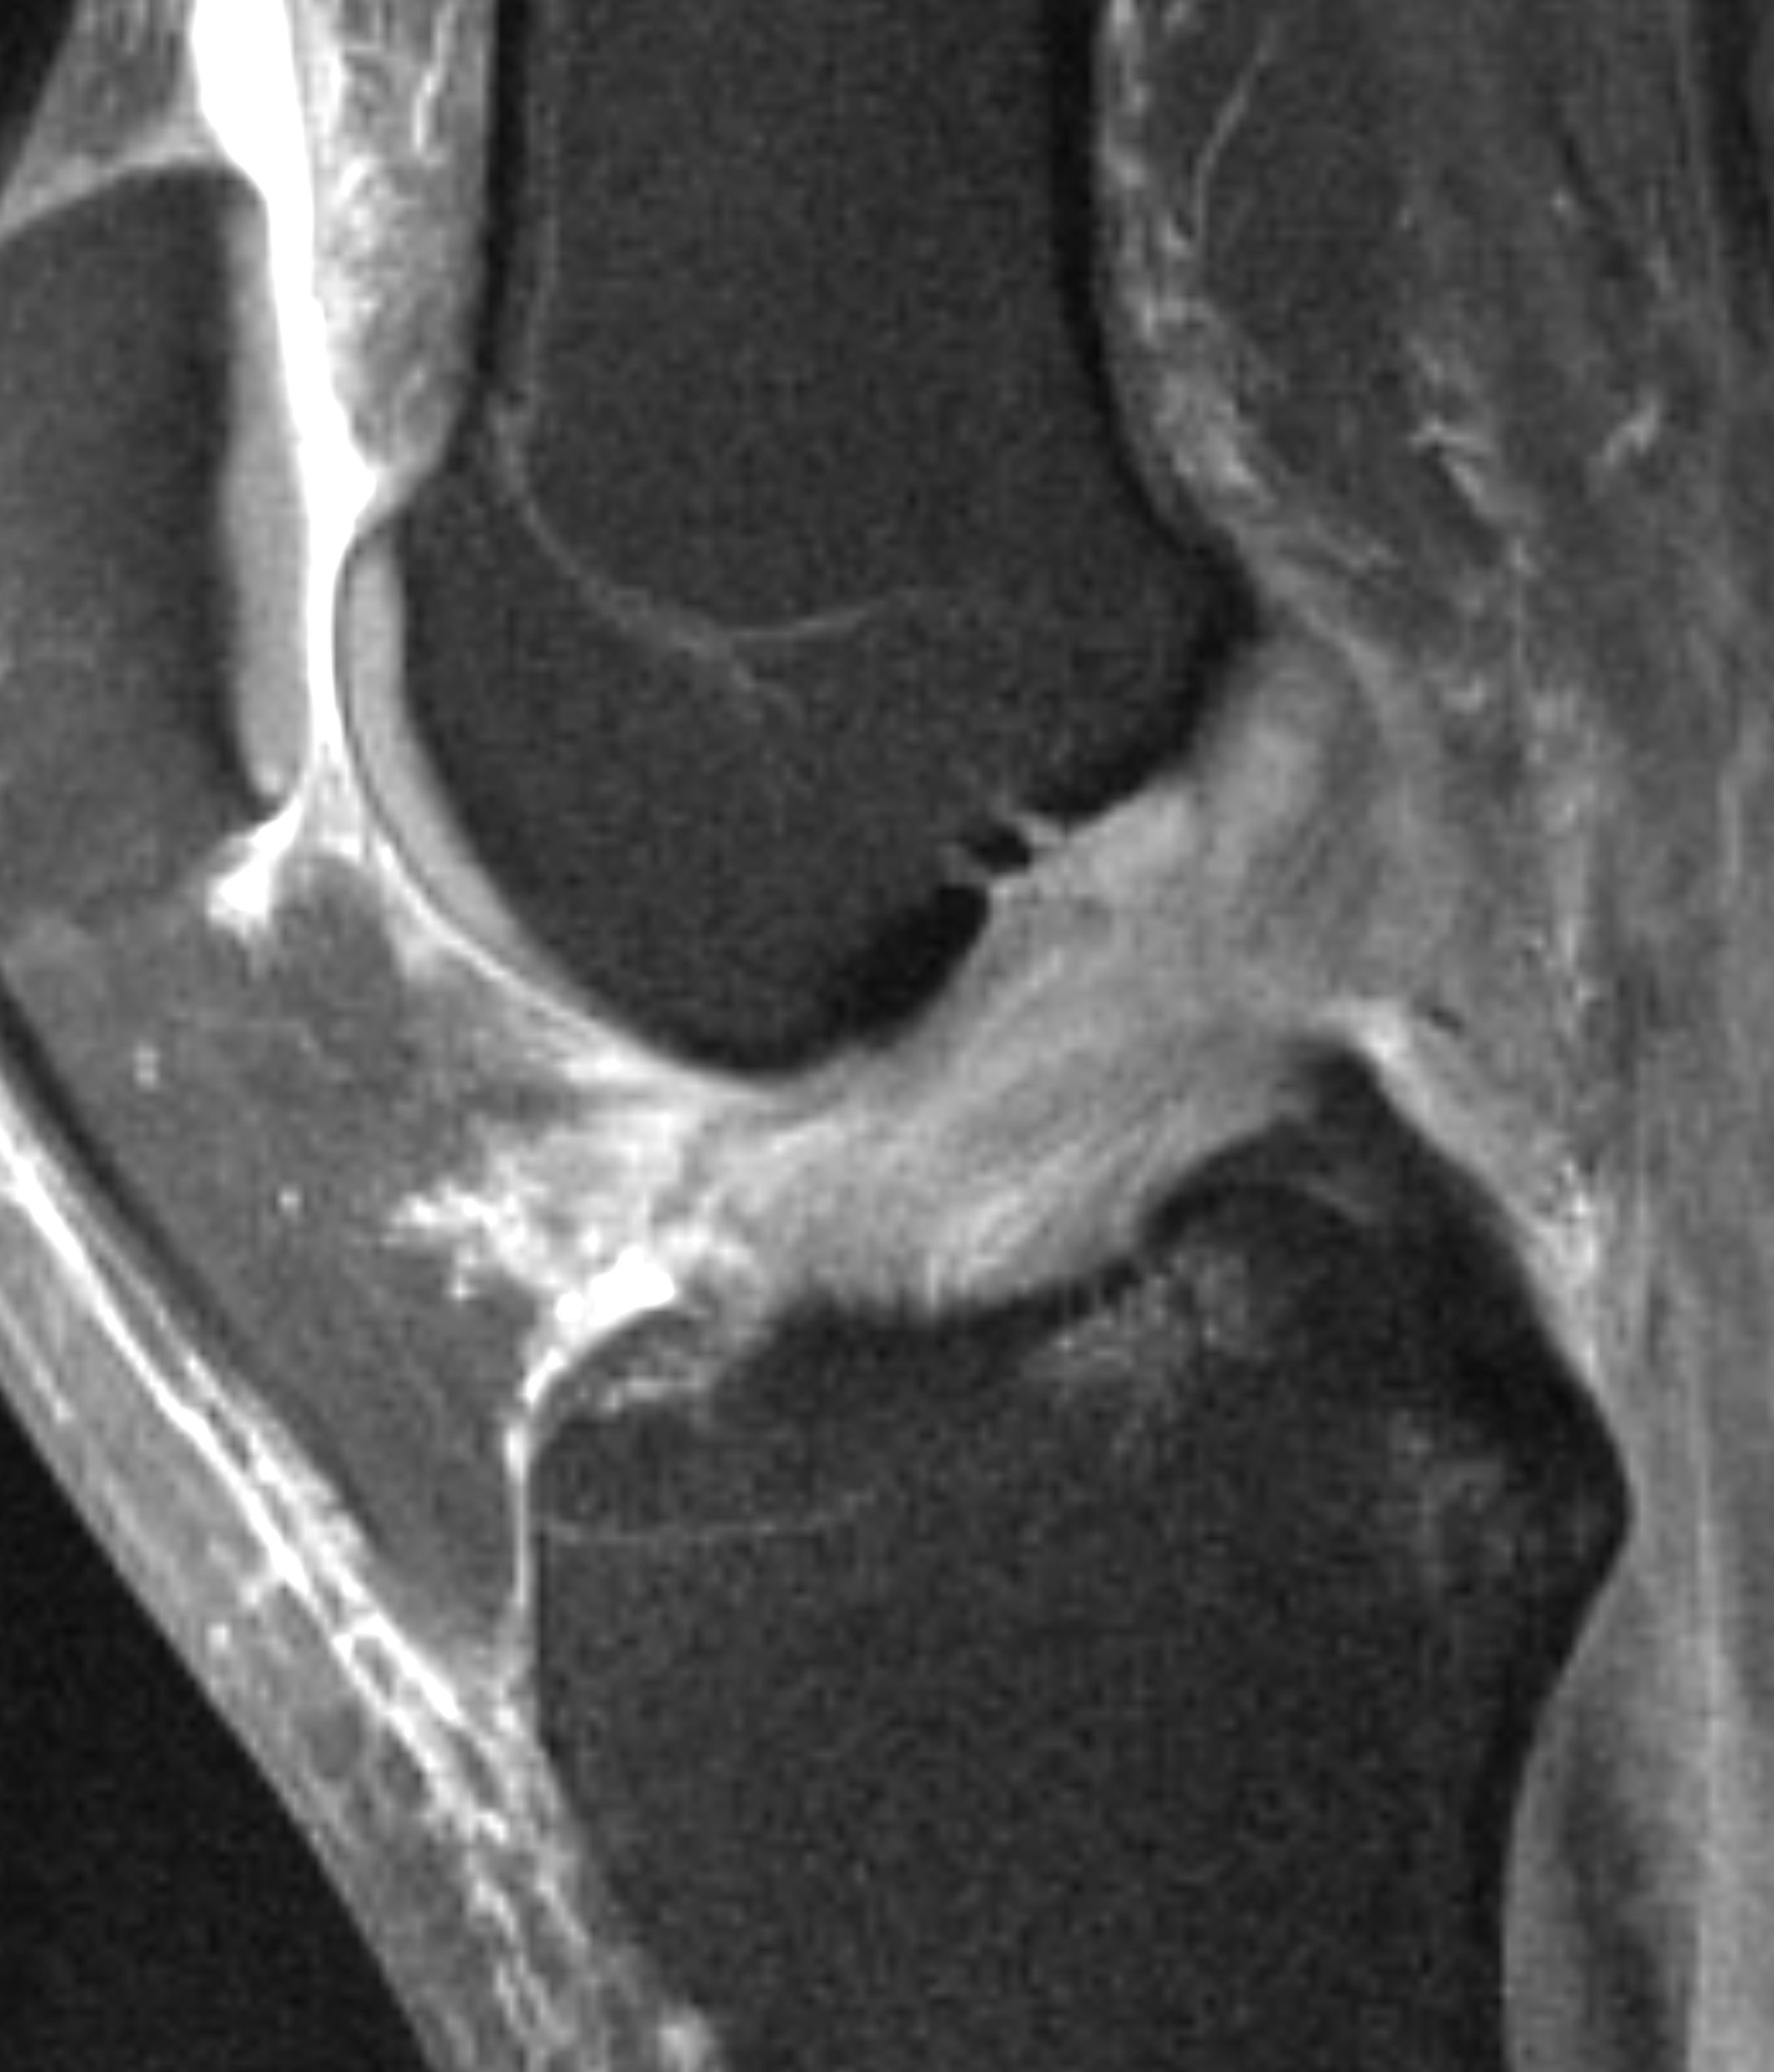

L’IRM est un complément indispensable pour confirmer le diagnostic, et surtout pour faire un bilan complet du genou à la recherche notamment de lésions méniscales associées.